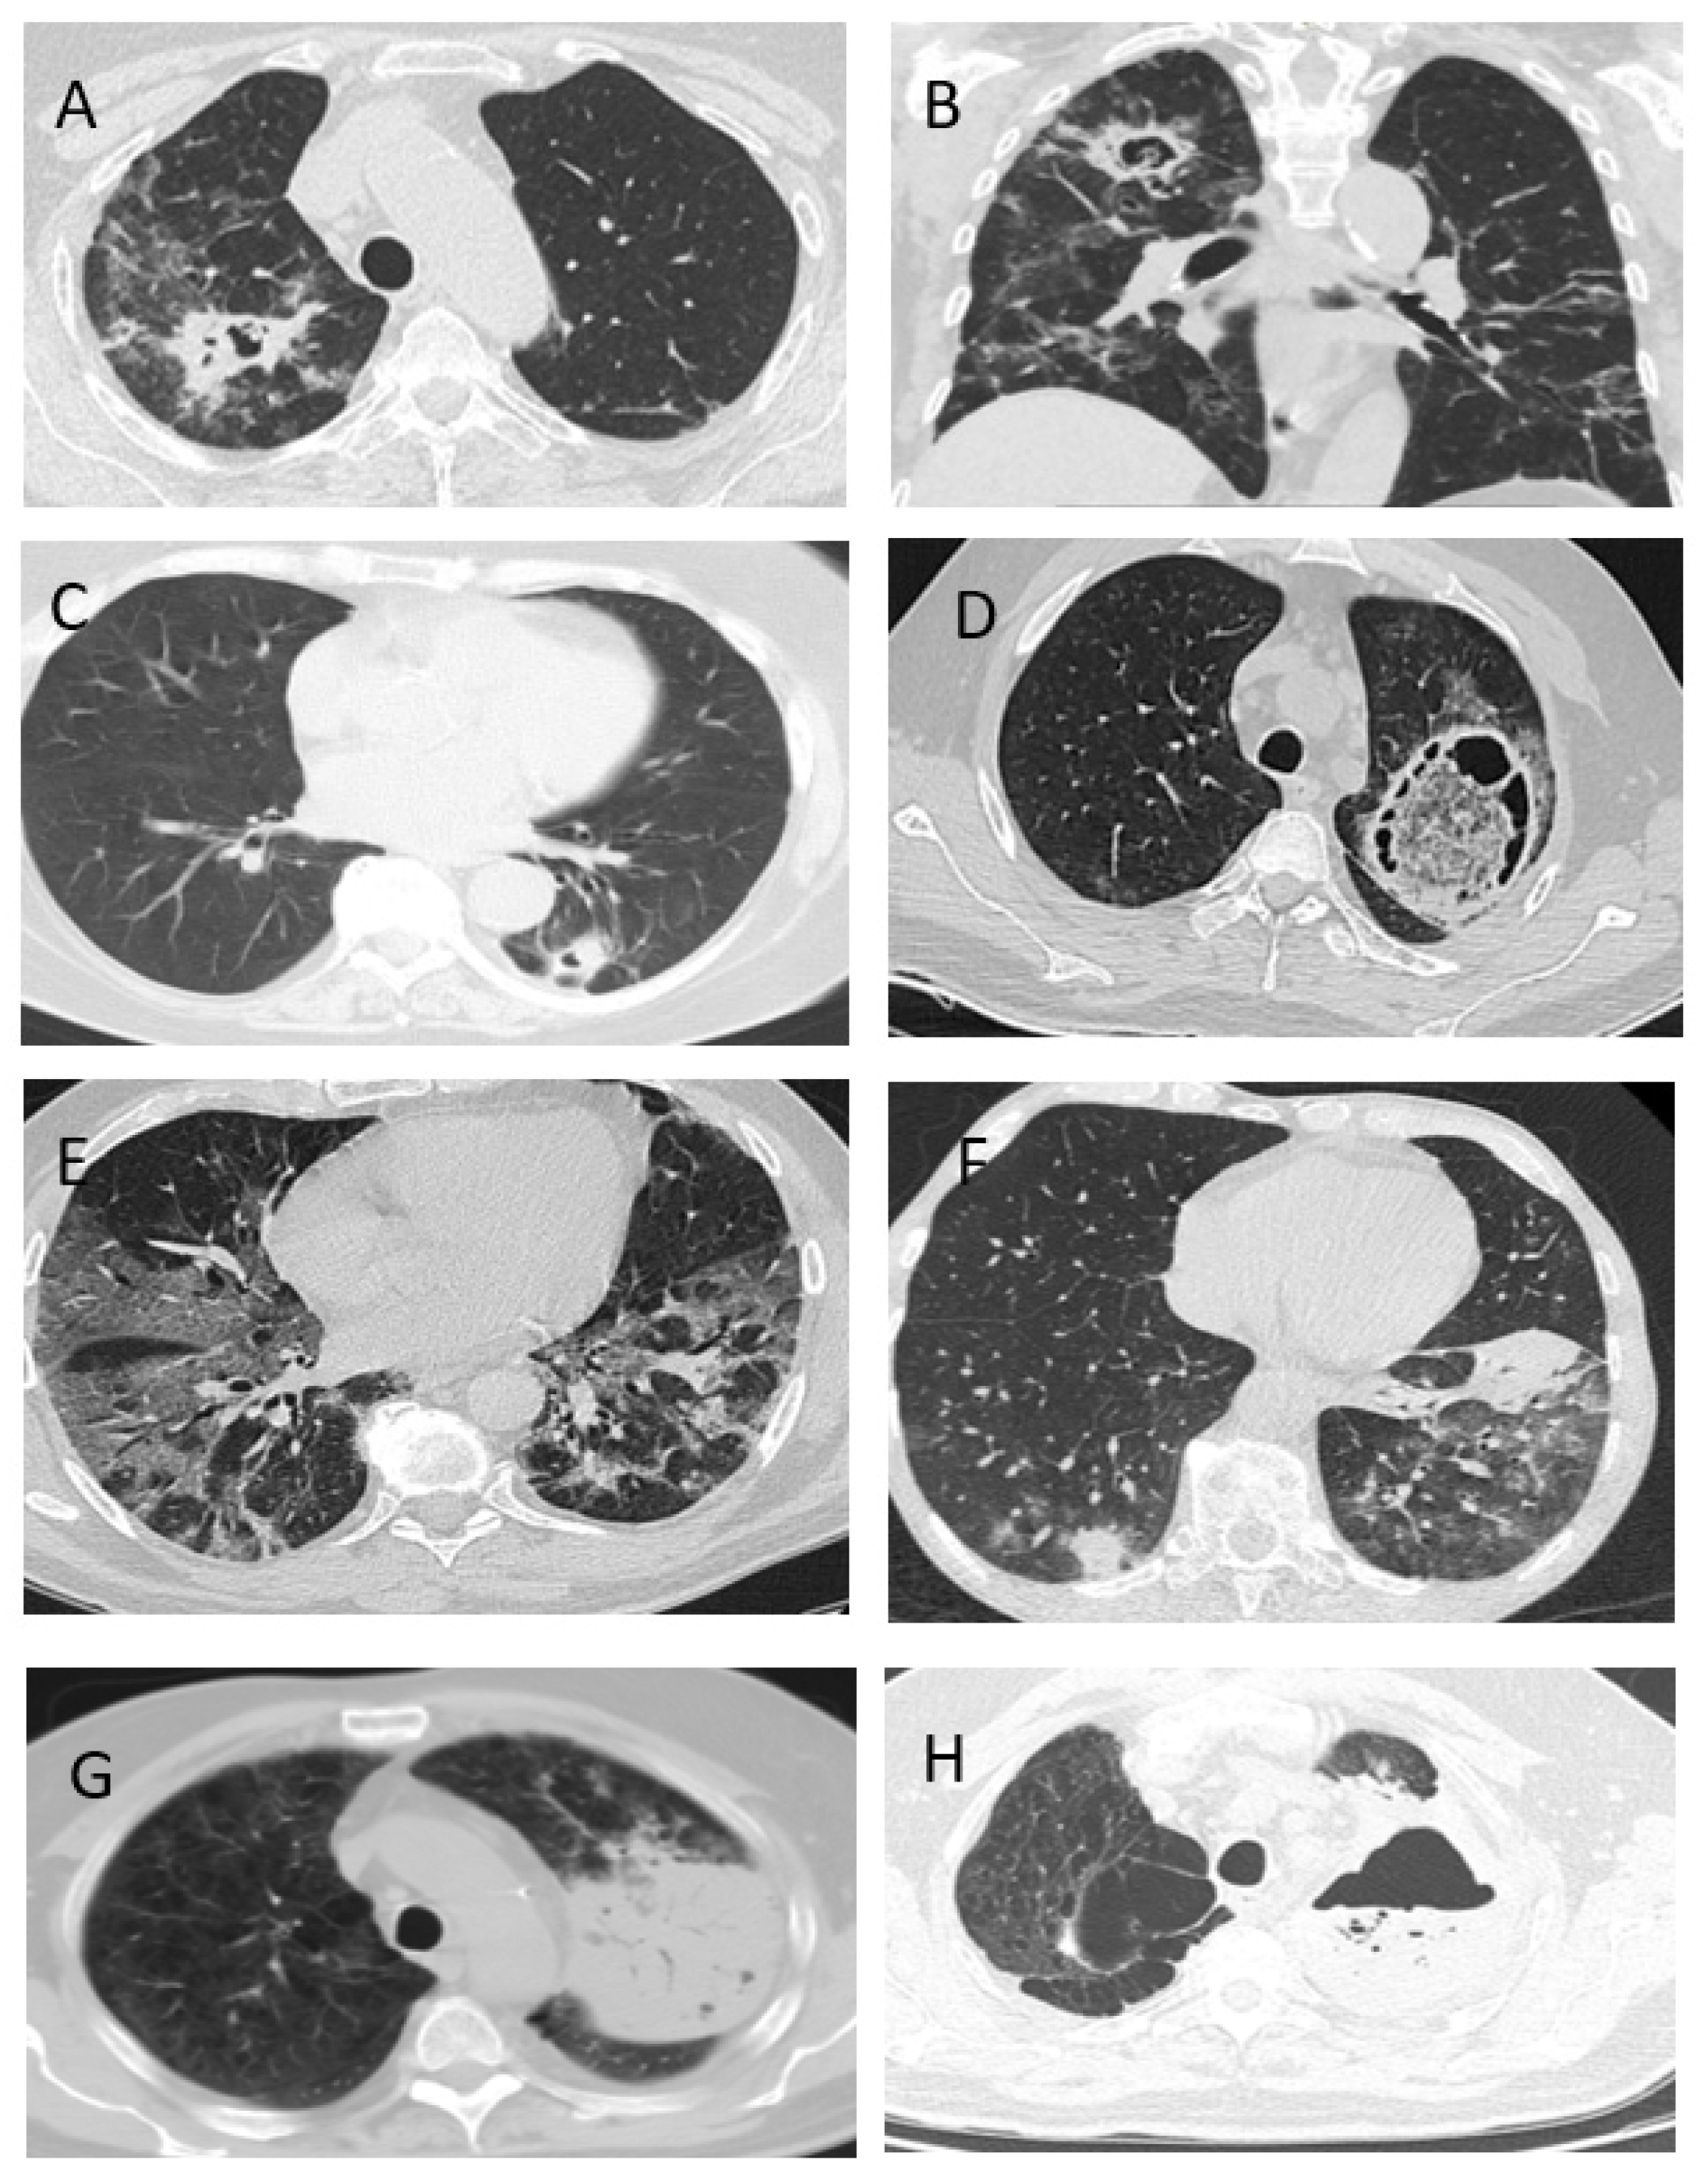

| CT-signs | |||||

| bilateral lesion | 42 | 93% | 75/80 | 94% | 0.8 |

| infiltrations | 40 | 89% | 37/63 | 59% | 0.004 |

| the “frosted glass” symptom | 33 | 73% | 64/80 | 80% | 0.3 |

| destruction cavity | 21 | 47% | 1 | 1% | 0.00001 |

| the “halo” symptom | - | - | - | - | |

| hydrothorax | 10/38 | 26% | 10/88 | 11% | 0.03 |

- The clinical signs of CAPA are nonspecific, but typically include: fever (98%), cough (89%) and hemoptysis (36%). The radiological signs of CAPA are foci of consolidation (89%) and destruction (47%), and hydrothorax (26%).